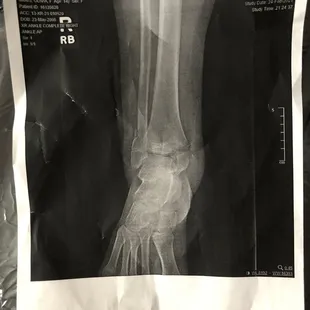

Her ankle was broken in two places.

The facility is unsafe.My sister broke her ankle because one of the makeshift structures fell onto her while playing. The owner was rude and unhelpful. He made sure to let us know he was protected by insurance and downplayed her injury.Don't come here. This place is not being run by someone who cares about your safety